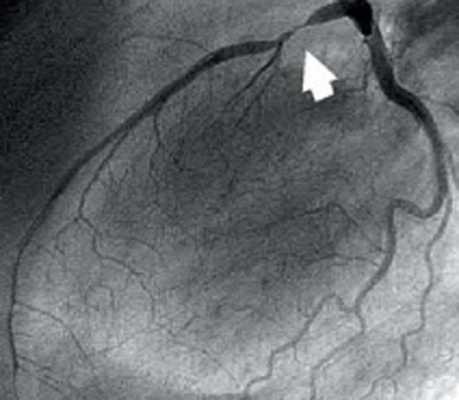

Артерии и вены сердца (ангиография, КТ).

Представлены коронарные артерии в латеральной проекции.

- Левая главная или левая коронарная артерия (ЛКА)

- Левая передняя нисходящая артерия (ЛПН)

- диагональные ветви (D1, D2)

- септальные ветви

- краевые ветви (M1,M2)

- Ветвь острого края (ОК)

- Ветвь АВ-узла

- Задняя нисходящая артерия (ЗНА).

Анатомия коронарных артерий используемая при ангиографии.